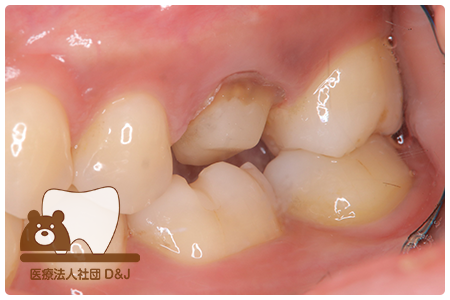

症例4フルジルコニアクラウン 左下6

治療前

治療後

37歳 男性

- 治療内容

- 以前のクラウンがセメントの劣化により外れた為その上にフルジルコニア製の被せ物を装着しました。見た目と強度を両立した自由診療の治療です。

- 治療期間

- 1カ月

- 費用

- 自費

フルジルコニアクラウン:77,000円(税込)

(R8.1月時点)

- その他の治療の費用は含まれておりません。

- リスク・副作用

- 硬い素材のため、かみ合う歯に負担がかかることがあります。将来取り外す場合に歯に負担がかかることがあります。強い力が加わると、まれに欠けたり割れたりすることがあります。